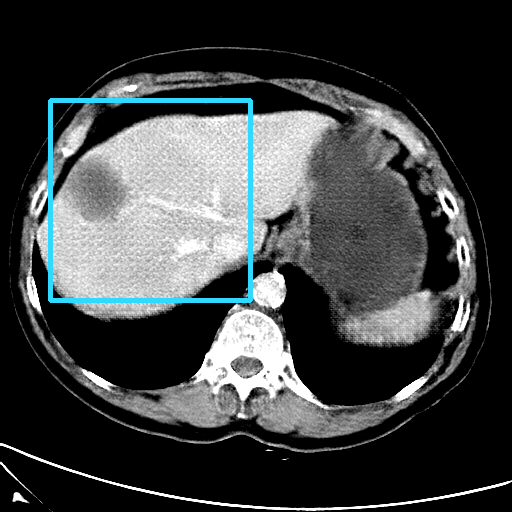

Refer to caption

(a) CT images.

(b) MRI images.

Figure 6: Lossy compression based attack on CT images (a) and MRI images (b) with a specific channel numbers (C8050\mathrm{C^{50}_{80}}) for the EP and IT Scenarios. StolenEPD1\mathrm{Stolen}^{\mathrm{D1}}_{\mathrm{EP}} denotes the decompressed images in the EP Scenario with a reduced D1 decoder.

Compression-Fidelity Compromise. Based on the previous results, we have selected the decoder D1D1 and the configuration of the latent and hyperlatent variables C8050\mathrm{C^{50}_{80}}, as the optimal architecture of the HiFiC encoder-decoder pair. In Fig. 6, we display more specifically the compression and reconstruction quality performances. In terms of reconstruction quality, we obtain a PSNR of approximately 40 for CT images and around 38 for MRI images while the MS_SSIM values are close to 1. This indicates an excellent perceptual quality of the reconstructed images that are hardly discernible from the original ones. In terms of compression efficiency, the Pratio\mathrm{P}_{\mathrm{ratio}} for CT images is approximately 0.015, indicating that the lossy image compression-based attack generated compressed images are 67 times smaller than those produced by the lossless zipped image compression-based attack. For MRI images, the Pratio\mathrm{P}_{\mathrm{ratio}} is around 0.12, 10 times higher than that of CT images, which can be attributed to the presence of a large uniform background in the skull-stripped original MR images.

A visual comparison between target and stolen images is available in Fig. 7. We observe that the stolen images from IT Scenario closely resemble the input ones, particularly in the tumor regions, whereas stolen images from EP Scenario exhibit blurring artifacts in finer details. In both cases, the stolen images reconstructed by D1D1 demonstrate a comparable quality to those reconstructed by DD, thus further confirming the effectiveness of the reduced decoder D1D1.